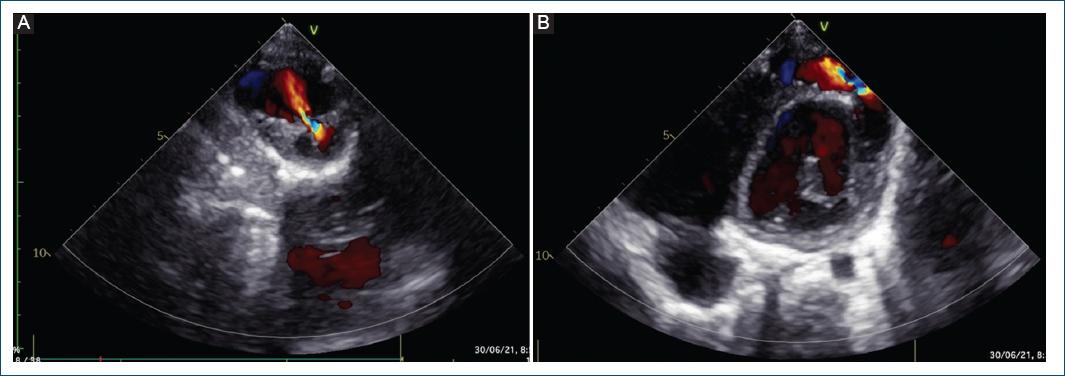

Se realizó ecocardiografía de control, en la cual se evidenció el aneurisma excluido (Fig. 3). Sin embargo, al año de seguimiento, mediante ecocardiografía se evidenció un defecto residual en el parche, con dos fugas residuales de 1.5 y 2.5 mm, con cortocircuito bidireccional en la punta del ventrículo izquierdo hacia la bolsa residual pericárdica, con función ventricular sistólica conservada, discinesia e hipocinesia de la punta ventricular izquierda (en el sitio del parche quirúrgico) (Fig. 4).

Figura 4 Ecocardiografía transtorácica. A: eje corto paraesternal, con evidencia de fuga residual en el parche de pericardio. B: eje apical de cuatro cámaras mirando al ápex, con evidencia de fuga residual.